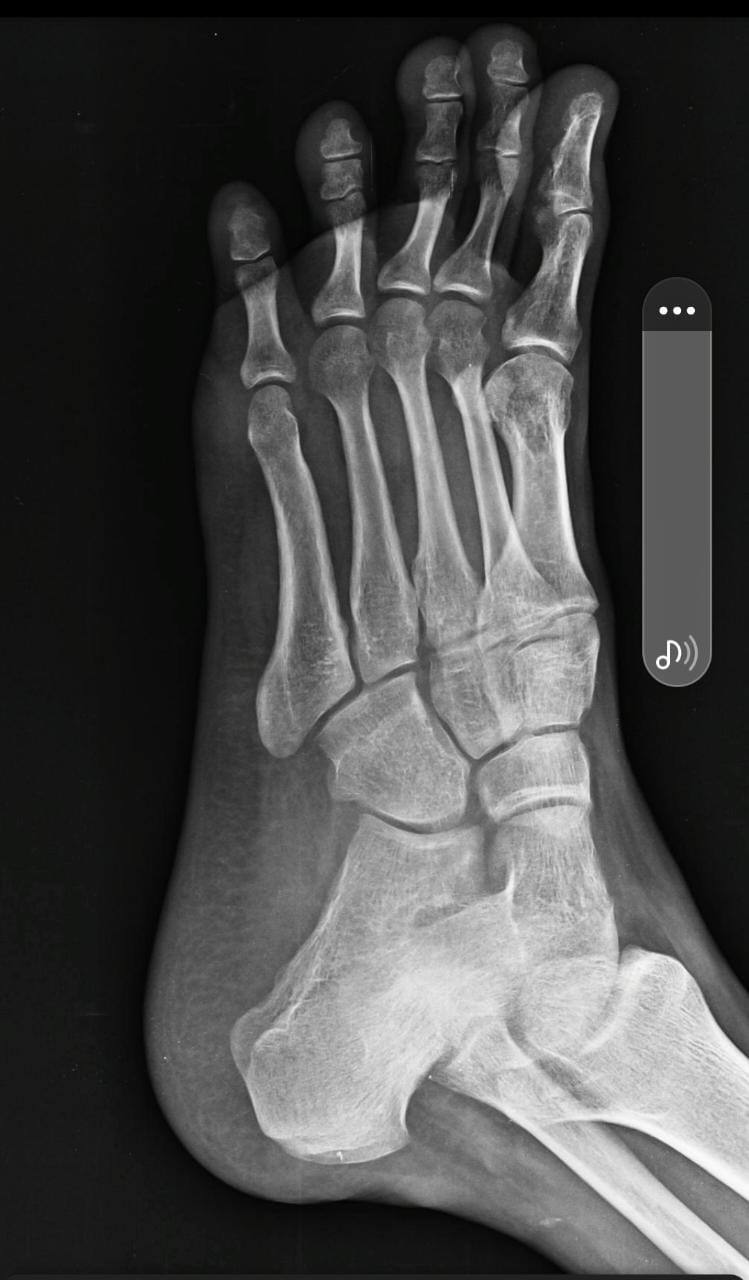

sir mera pair tree month pehale akel se mud gaya tha aur tisara x ray bhej rha hu kuch injury ho to bataye